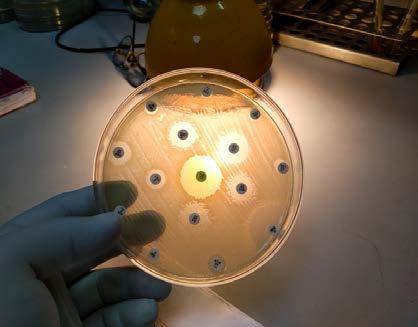

Care where you want it. Strep Cultures . Flu, Covid & RSV Testing . Seasonal Allergies . Prescription Refills . Ear Exams . Rashes & Pink eye . Urine Cultures . Labwork. SERVIC I N GSTAC&NYLKOORB K I LL AREAS CARE AT HOME Sun: 12pm-6pm | Mon-Thurs: 3pm-10pm | info@medease.care | medease.care | 718.208.2030 Forget about waiting rooms. Get quality care at home. TELEHEALTH VISITS WHEN A PHONE CALL IS ENOUGH We accept most insurance plans